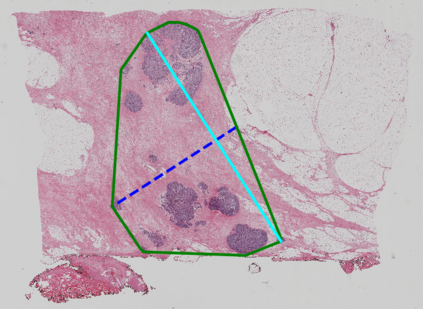

Whole slide images (WSIs) pose unique challenges when training deep learning models. They are very large which makes it necessary to break each image down into smaller patches for analysis, image features have to be extracted at multiple scales in order to capture both detail and context, and extreme class imbalances may exist. Significant progress has been made in the analysis of these images, thanks largely due to the availability of public annotated datasets. We postulate, however, that even if a method scores well on a challenge task, this success may not translate to good performance in a more clinically relevant workflow. Many datasets consist of image patches which may suffer from data curation bias; other datasets are only labelled at the whole slide level and the lack of annotations across an image may mask erroneous local predictions so long as the final decision is correct. In this paper, we outline the differences between patch or slide-level classification versus methods that need to localize or segment cancer accurately across the whole slide, and we experimentally verify that best practices differ in both cases. We apply a binary cancer detection network on post neoadjuvant therapy breast cancer WSIs to find the tumor bed outlining the extent of cancer, a task which requires sensitivity and precision across the whole slide. We extensively study multiple design choices and their effects on the outcome, including architectures and augmentations. Furthermore, we propose a negative data sampling strategy, which drastically reduces the false positive rate (7% on slide level) and improves each metric pertinent to our problem, with a 15% reduction in the error of tumor extent.